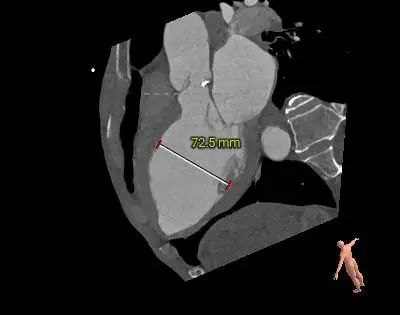

术前CT评估

1.CT数据显示该患者为TYPE1二叶式主动脉瓣,瓣叶增厚伴中重度钙化,右无瓣之间有钙化嵴,钙化主要分布在瓣叶上。

2.主动脉瓣瓣环周长100.1mm,平均周长径31.9mm。

3.左心室收缩和舒张期前后径均大于70mm,心室壁较薄,术中发生恶性心律失常风险大,预装瓣膜,备自动除颤仪和ECMO。

主动脉根部测量

冠脉阻挡风险及左室大小评估